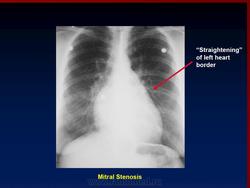

На ЭКГ выявляют митральную форму зубца Р (гипертрофия левого предсердия), признаки гипертрофии правого желудочка, позднее — мерцательную тахисистолию. На ФКГ регистрируются диастолический шум с пресистоличе- ским усилением, высокая амплитуда I тона, щелчок открытия митрального клапана, удлинение интервала Q — I тон от 0,08 до 0,1 с. На эхокардиограмме (М- сканирование) выявляют П-образную форму клапана. При рентгенологическом исследовании обнаруживают сердце митральной конфигурации — (сглаженность талии за счет выбухания дуг левого предсердия и легочной артерии), усиление сосудистого рисунка (линии Керли), отклонение контрастированного пищевода по дуге малого радиуса. В части случаев точная инвазивная диагностика порока достигается путем пункции левого предсердия, позволяющей выявить увеличенный предсердно- желудочковый диастолический градиент. Ценную информацию дают катетеризация сердца и рентгеноконтрастное исследование.